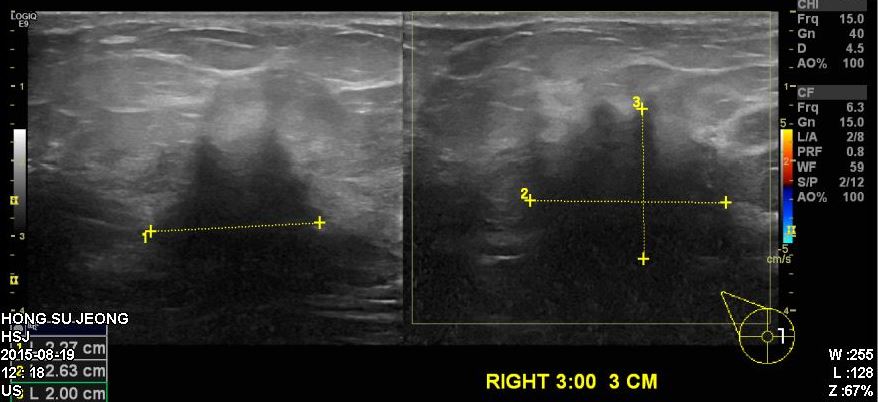

우측 유방에  만져지는 몽우리로 내원하신 60대 여성 분으로 우측 유방 3:00시 방향에서

3cm 거리의 의심스러운 혹 조직검사 시행하였으면 우측 침윤성 유관암 진단 되었습니다.